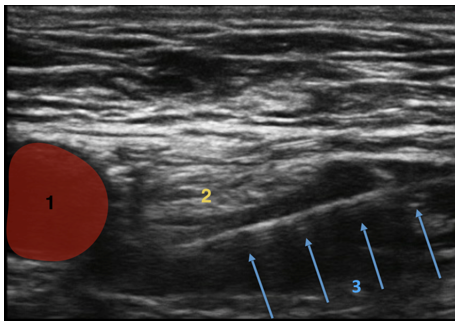

大腿神経ブロック - 針のガイドの画像

左脚 – 外側から内側へのアプローチ

大腿動脈

大腿神経

針